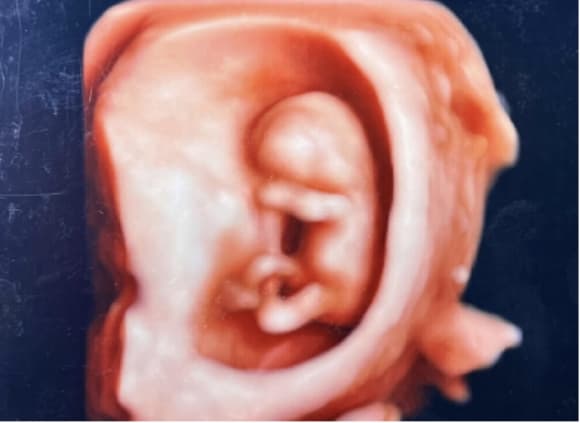

臍帯の首への券絡3回(3D血管エコー)

4D胎児エコー写真

4Dエコー外来

• 妊婦健診の中でいつでもご希望の時に、お腹の中の赤ちゃんの状態を立体的に、そして動きまでリアルにご覧いただける超音波技術を用いた4Dエコー外来が受診できます。

• お腹の中のお子さまの様子を鮮明にご覧いただくことが可能です。(希望者のみ:2,160円/回)

※当日の胎児の向きや、姿勢によって必ずしも顔がはっきり見られるとは限らないため、費用は見えたときのみいただいております。

(30週)

(36週)